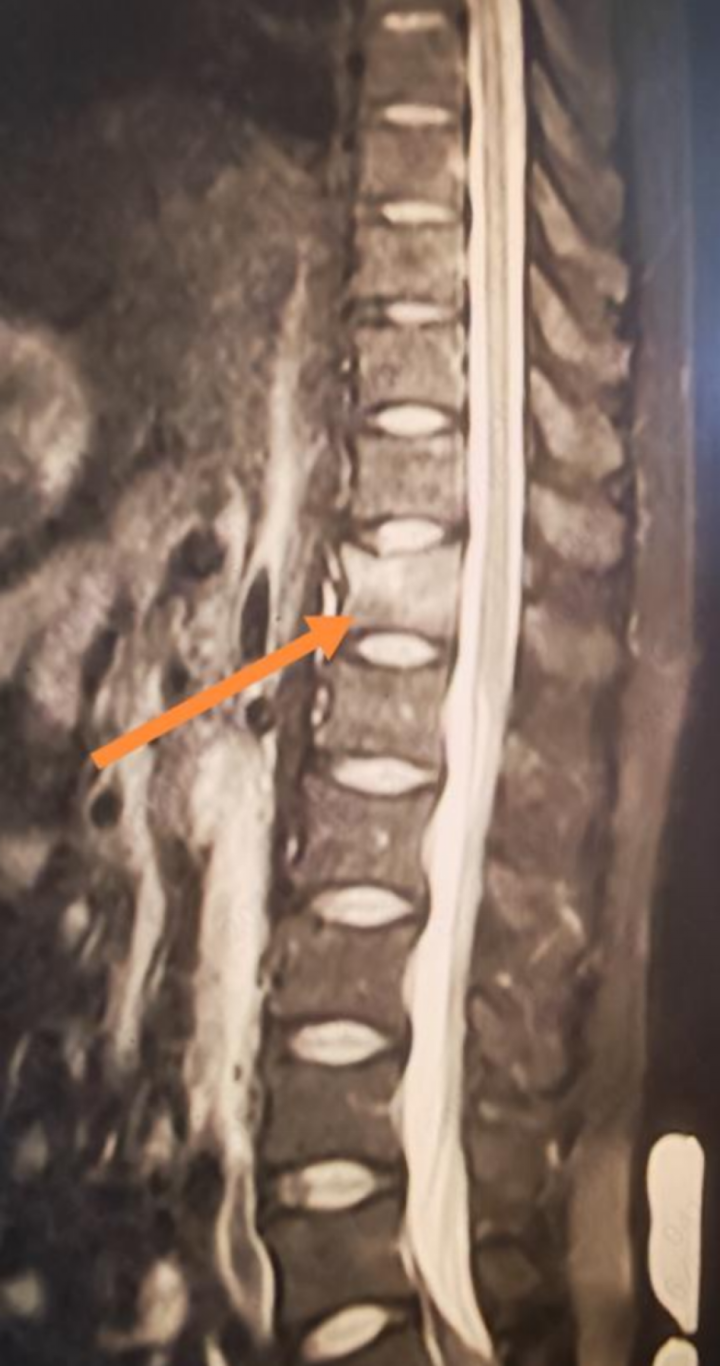

拿到核磁报告的那一刻,李先生彻底傻眼:胸12椎体压缩性骨折。